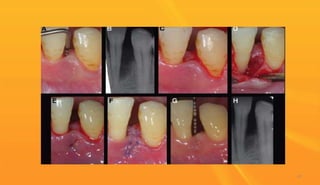

 Pocket lining was removed with the help of a diode laser

 The laser setting used for this procedure was 4 W in

continuous mode.

 Crevicular incision was given with a bard parker # 15 blade

directed toward the alveolar crest.

 Full thickness mucoperiosteal flap was raised buccally and

lingually.

 The granulation tissue was removed from the defects by

manual debridement .

 Reduction in probing depth was from 11 mm to 6 mm.

 Radiographs revealed increased bone fill.

Laser - assisted modified Widman flap (LAMWF) – Case report

Removing the pocket lining with diode laser

[ sanjeev et al – 2010]